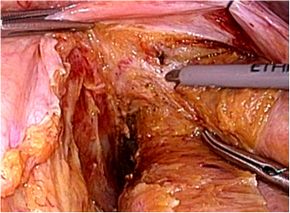

腹腔鏡下結腸・直腸切除術の実際

全身麻酔下で手術を行います。まず腹腔内(腹腔:お腹の壁と臓器との間の空間のことで

す)に炭酸ガスを入れて膨らませ、お臍からカメラ(腹腔鏡)を挿入します。この際、同

時に手、術操作に用いる器具(鉗子など)を挿入するために、5〜10mmの小さな穴を左

右に4ケ所開けます。そして腹腔鏡で撮ったお腹のなかの様子をモニターに映し出して、

大腸切除や周囲のリンパ節の切除を行います。開腹手術では見えにくかった細かい血管

や神経まで見えて繊細な手術操作が可能です。実際の腹腔鏡手術は、開腹手術と同じ全

身麻酔下で行います。

この手術は、専用の高性能カメラからの拡大した鮮明な画像を見ながら行うため従来の、

開腹手術では見えにくかった部位や細かい血管・神経まで見えて繊細な手術操作が可能

です。腹腔内で操作を終えたあとに最後に臍切開創を4−5cmに延長し病変をお腹の外

に取りだします。

結腸切除術の場合は体外で、直腸切除術の場合は体内で吻合(腸と腸をつなぐ)を行いま

す。特に直腸がんの場合、肛門温存術に関しては、非常に肛門に近くて従来なら永久人

工肛門となっていた超低位の直腸がんに対しても肛門縁から2〜3cmほど距離があって

一定の条件を充たせば、永久人工肛門を極力避けて自分の肛門を残す超低位直腸切除術

を積極的に行っています。